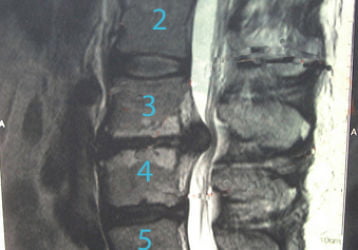

Что такое циркулярная протрузия диска: виды и стадии болезни, схемы лечения

Что такое циркулярная протрузия диска: стадии болезни, разновидности. Ее признаки, симптомы, методы диагностики и способы лечения протрузий дисков.